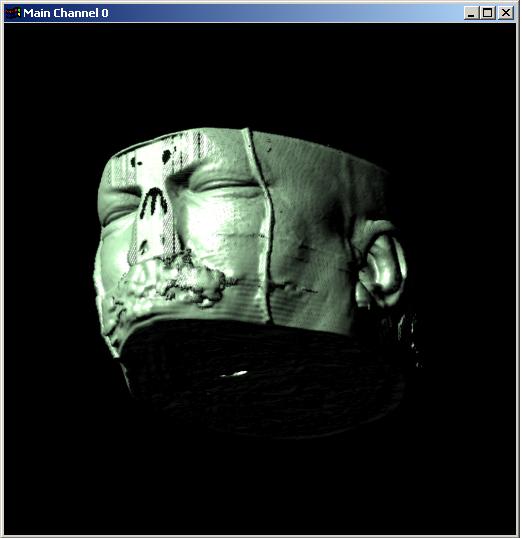

Visible human male CT data

Data

Resolution : 256x256x128

Visible human male CT data

Skin only

Data Resolution : 256x256x128

The following 12

images was generated by PC which has NVIDIA's GeForce3 GPU graphics card. The

hardware accelerated rendering techniques are used to make the following images.

To use the GeForce3 hardware, we have to use the OpenGL extensions like

GL_NV_texture_shader2, GL_NV_register_combiners, GL_EXT_texture3D,

GL_EXT_paletted_texture, GL_ARB_multitexture and so on. Since the GeForce3 card

allows the 3D texture shading, the image quality is better than the pixel of

frame buffer based shading in showing two materials at the same time.